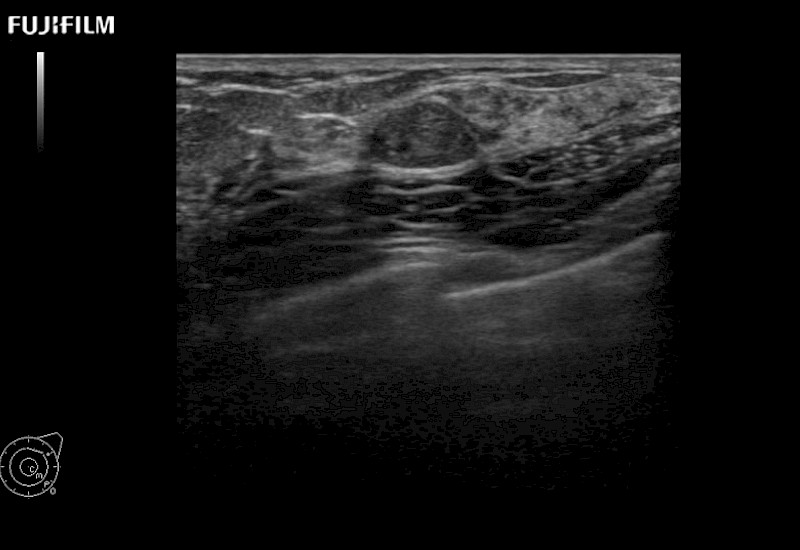

Extraordinary high-resolution digital imaging

Multi-Parametric imaging modalities

Our dedication to Surgical Oncology allows us to offer superior image quality, outstanding system reliability and intuitive use of cutting edge technology.

The ARIETTA 750 incorporates all of the proven technologies and functions that medical professionals have come to expect from Fujifilm Healthcare.

ARIETTA 750 is the definitive diagnostic ultrasound solution for any clinical setting - Private Office, Imaging Center, or Hospital. The ARIETTA platform provides the ultimate in clinical performance with its state-of-the-art features and large user-friendly display.

The ARIETTA 650 DI combines trusted Fujifilm Healthcare technologies and features tailored for surgical oncology.

Designed to meet the demands of surgeons, the ARIETTA 650 DI offers precise guidance. Its advanced capabilities and large, intuitive display offer accurate and efficient care in operating rooms and specialized surgical settings.